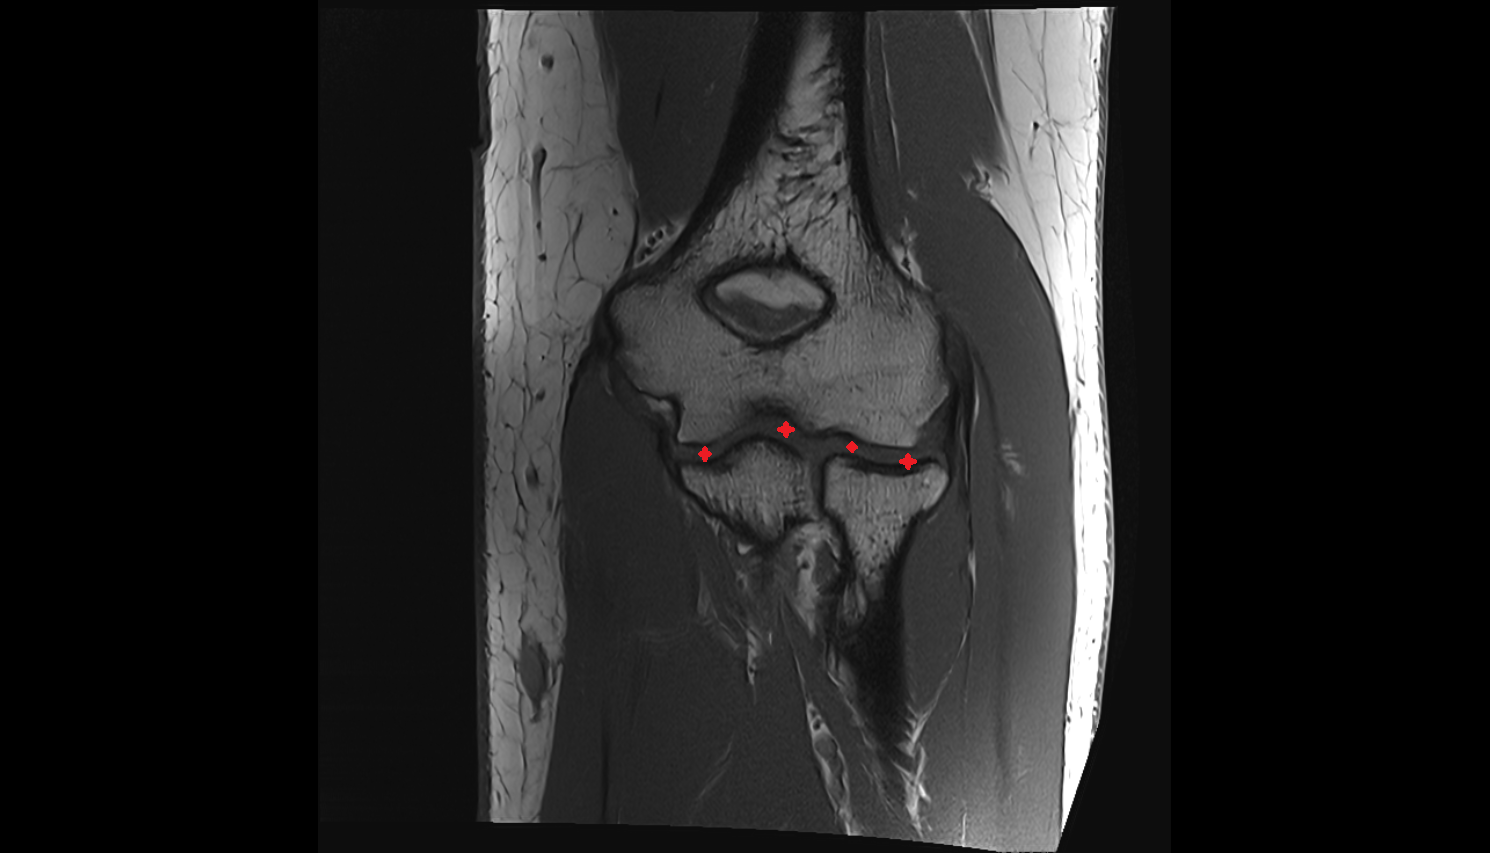

- Elbow joint

- Capitulum of humerus

- Trochlea of humerus

- Joint capsule of elbow

- Medial epicondyle of humerus

- Lateral epicondyle of humerus